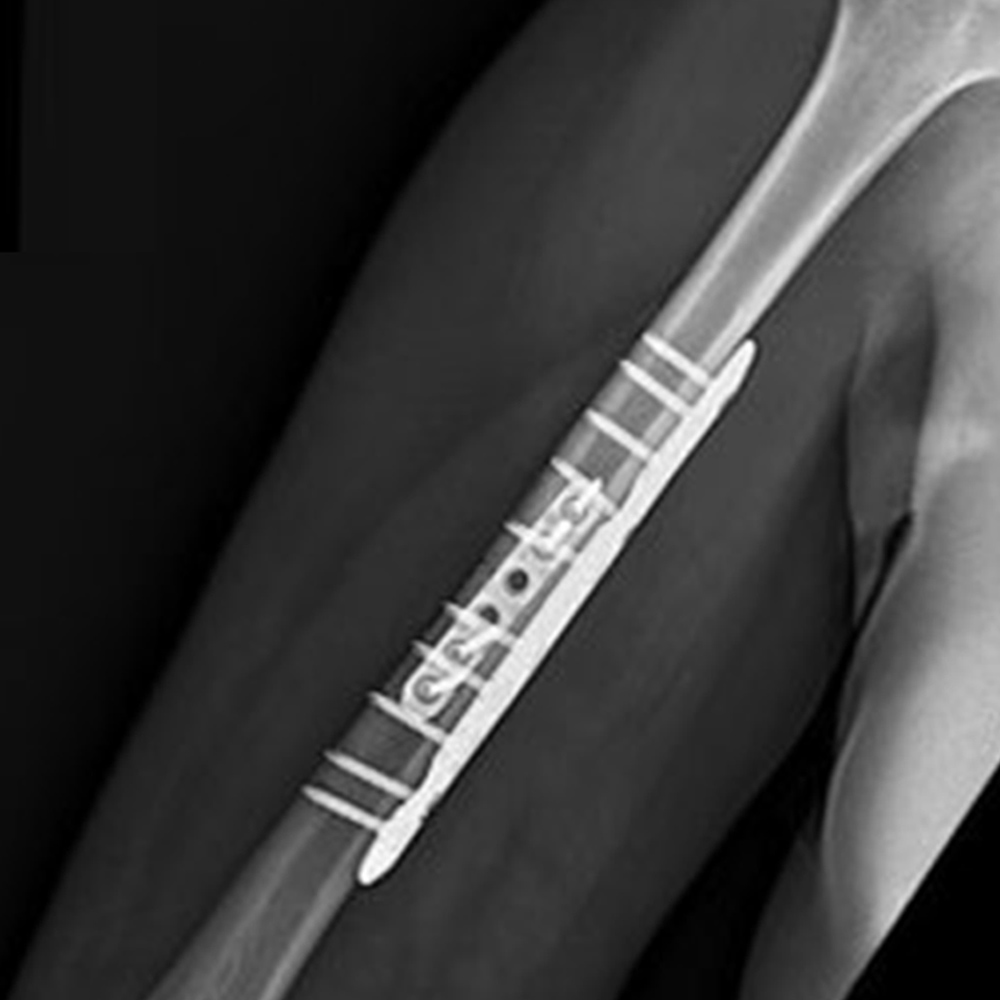

Midshaft Solutions

Plating System

- 40° Polyaxial locking

- Strong & consistent locking mechanism

- Low profile construct

- Titanium low-profile construct

- Locking caps allow all screws to compress the plate to bone before locking

- Locking caps improve fatigue properties and prevent screw back out

- Precise screw placement independent of plate position

- A single screw can be used to lag and then be locked into place without changing screw or disrupting reduction

- Polyaxial drill guides allows for provisional K-wire fixation

- The low profile design allows for optimal contour of the plate proximally